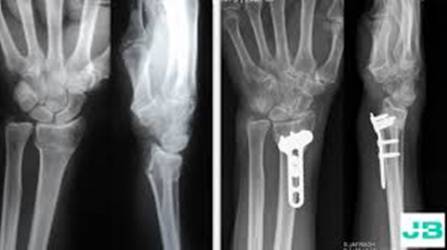

Los materiales que se emplean, principalmente, para ayudar a curar heridas son: esponjas de colágeno que ayudan a tratar las quemaduras y las úlceras por presión, y se usan implantes similares a los andamios para reparar huesos rotos. Sin embargo, el proceso de reparación de tejidos cambia con el tiempo, por lo que los científicos buscan biomateriales que interactúen con los tejidos a medida que se produce la curación.